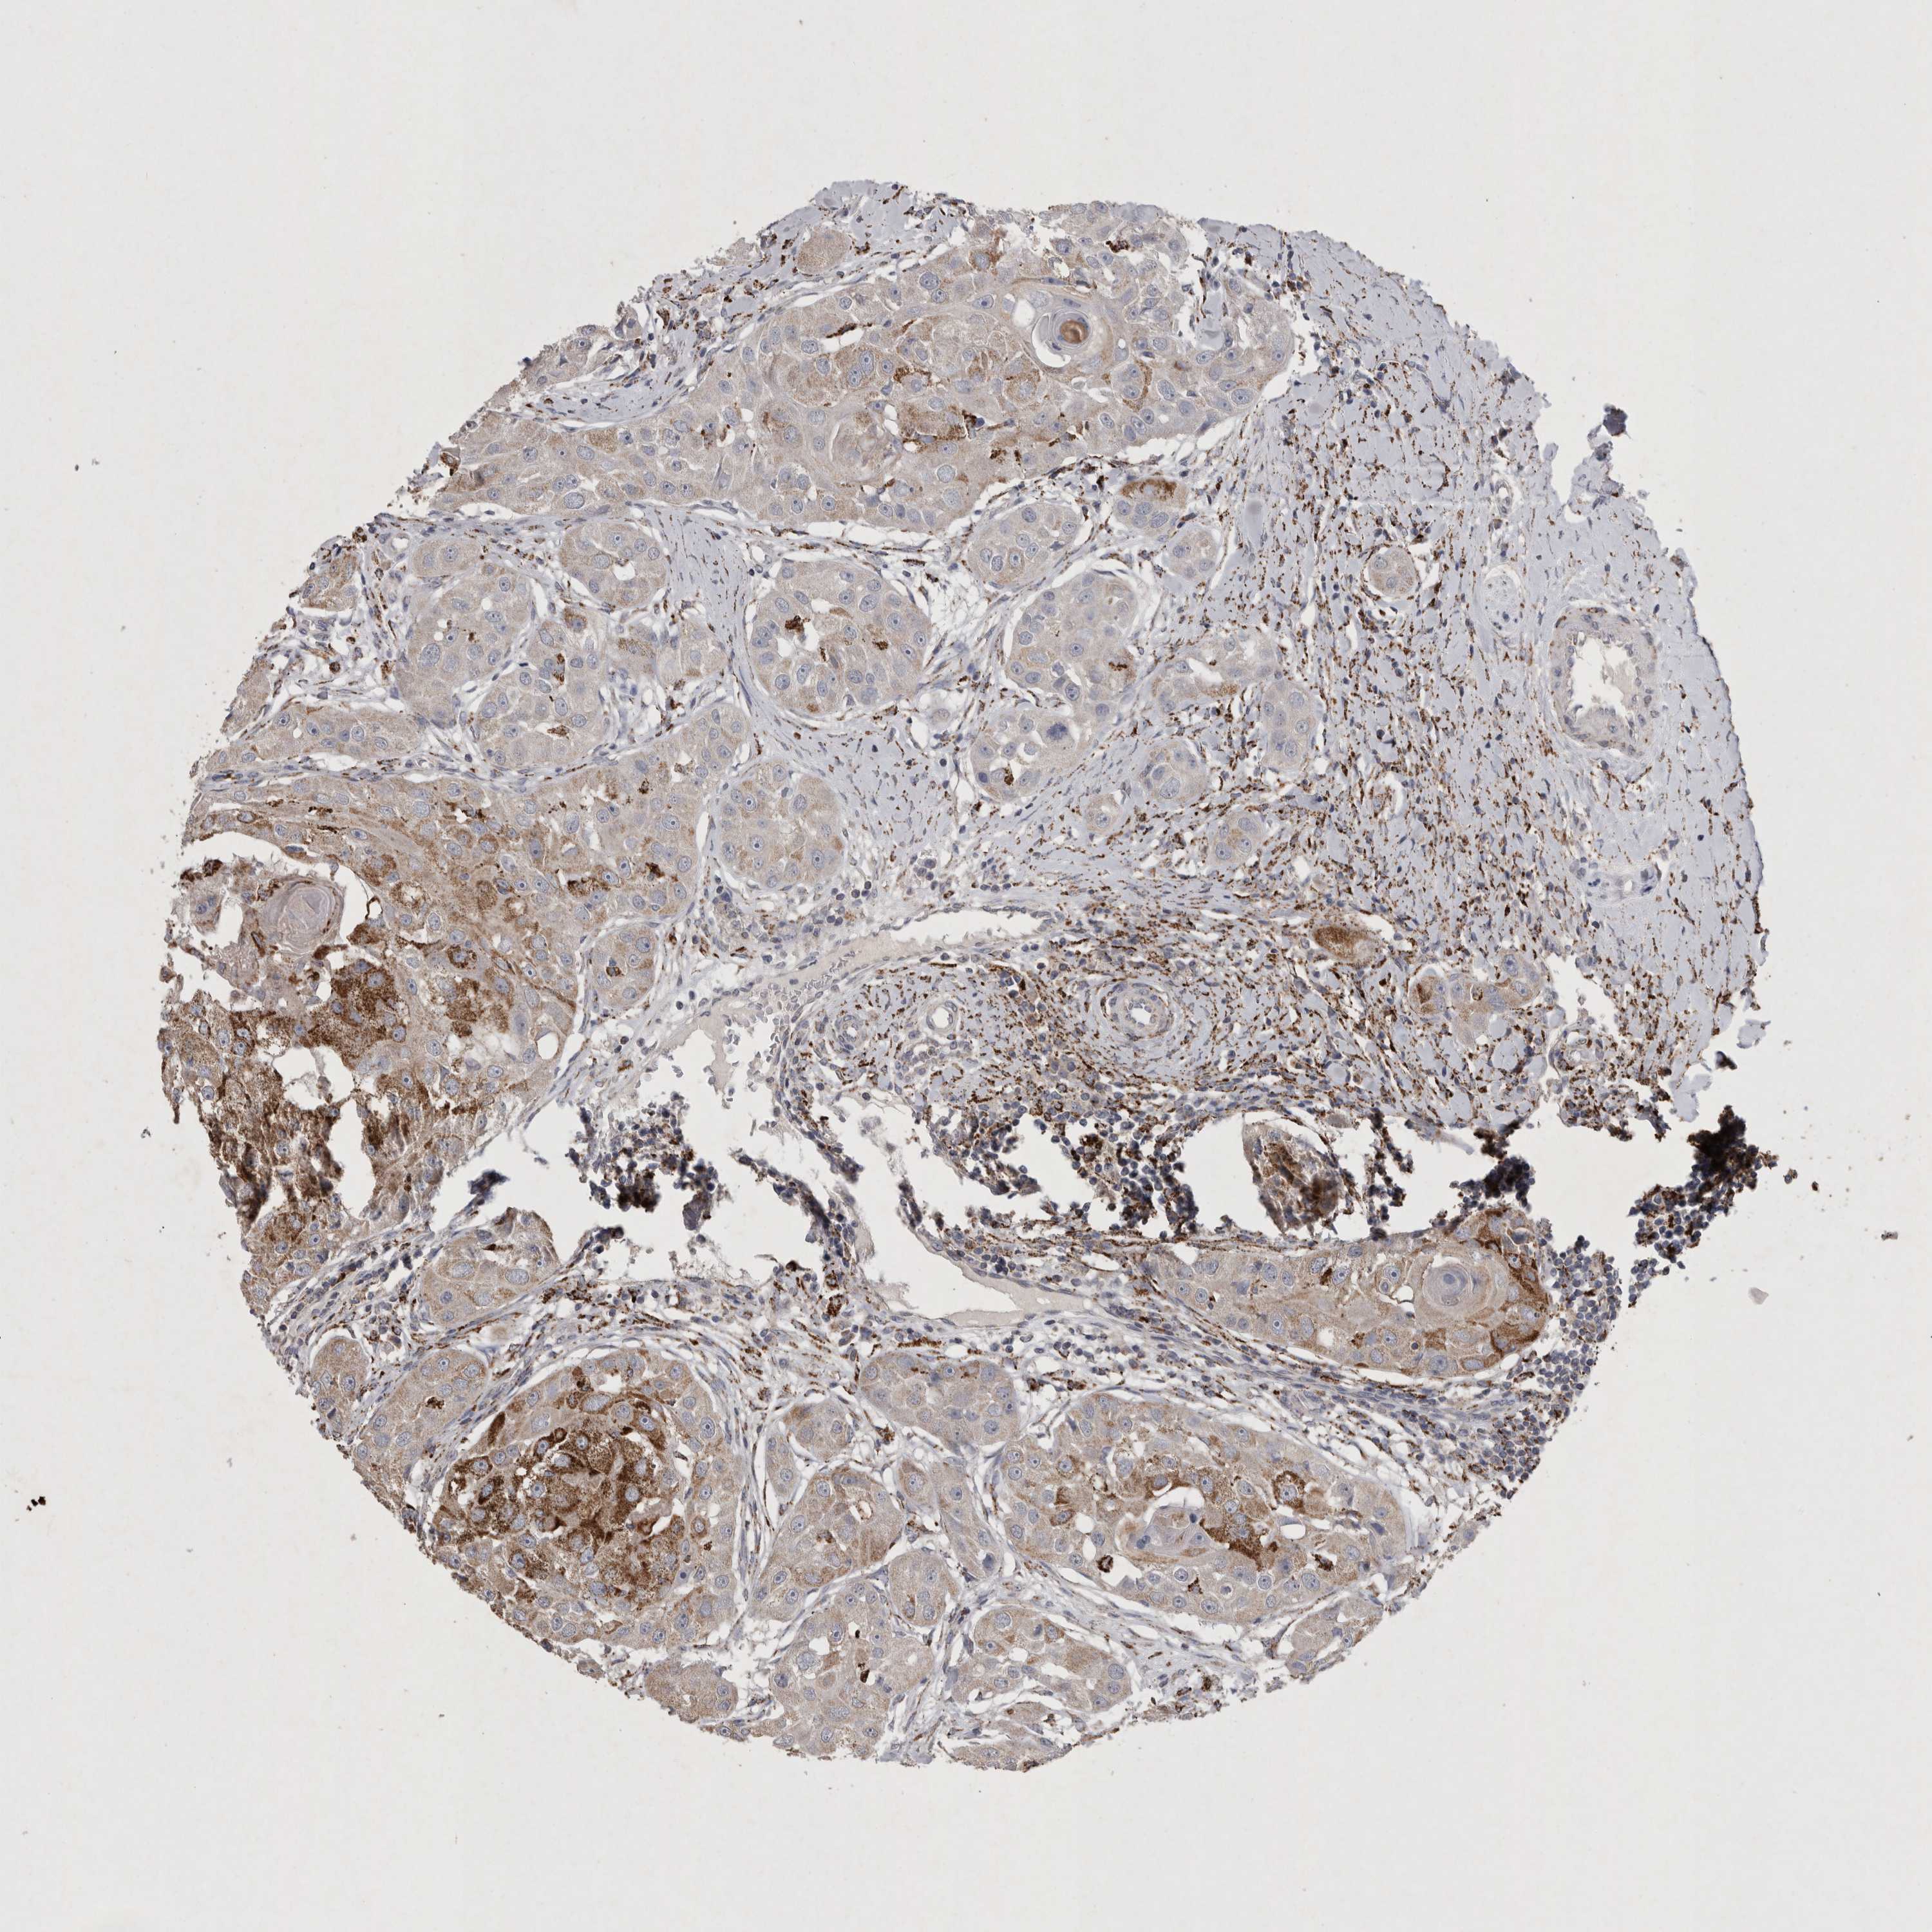

HEAD AND NECK CANCER - Protein expressioni

A mouse-over function shows sample information and annotation data. Click on an image to view it in a full screen mode. Samples can be filtered based on level of antibody staining by selecting one or several of the following categories: high, medium, low and not detected. The assay and annotation is described here.

Antibody stainingi

Antibody staining in the annotated cell types in the current human tissue is reported as not detected, low, medium, or high, based on conventional immunohistochemistry profiling in selected tissues. This score is based on the combination of the staining intensity and fraction of stained cells.

Each image is clickable and will lead to virtual microscopy that enables deeper exploration of all samples and also displays staining intensity scores, fraction scores and subcellular localization as well as patient and tissue information for each sample.

Antibody HPA011868

Antibody CAB024949

Staining

High

Medium

Low

Not detected

Intensity

Strong

Moderate

Weak

Negative

Quantity

>75%

75%-25%

<25%

None

Location

Nuclear

Cytoplasmic/membranous

Cytoplasmic/membranous,nuclear

Squamous cell carcinoma, NOS

Squamous cell carcinoma, metastatic, NOS

Adenocarcinoma, NOS

Adenoma, NOS